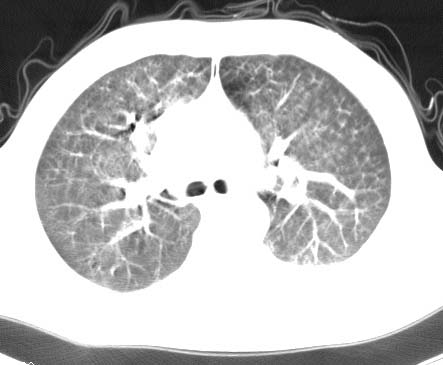

男性 病人 30岁,活动后气促2月余.隔疝伴胸腔积液.右上肺结核!

双肺上结核;膈肌裂孔疝。

左侧胸腔积液,并胸腔内见多个含液 气组织,并相互重叠。影像特征很特殊,应该是“膈疝”。支持!

左侧膈疝,及左侧胸水,双上肺结核。

支持!左侧膈疝,左侧胸水,双上肺结核。